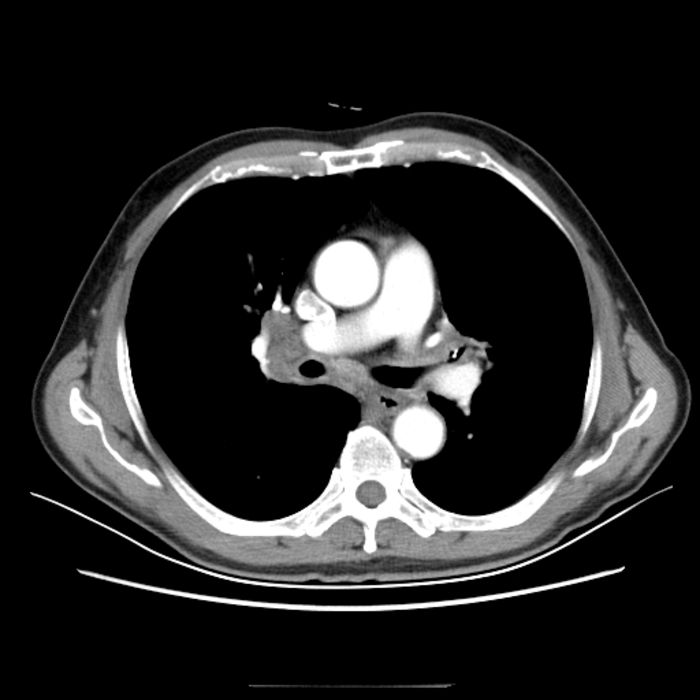

辅助检查:血常规:白细胞20.05×109/L;中性粒细胞77.3%;红细胞、血小板正常。胸部CT如下:

胸部CT未见明显异常,于是我们给他做了支气管镜检查,在患者左肺上叶支气管发现了支气管异物——鱼刺。

图6-7

支气管镜下发现异常后,我们再仔细回看做支气管镜检查前的胸部CT:

图8

可能有经验且细心的同道发现了该病灶,但如果这张图是放在没有任何提示的361张图片里,你确定还能发现病灶吗?当时影像科和临床医师都没有发现,如果我不做标识,相信非常多的人也看不出来。

图9

这个病例真实的警示我们,不明原因的胸闷、气短、呼吸困难,包括长期咳嗽,特别是胸部CT显示长期在固定部位出现肺不张或反复感染者,支气管镜检查更是不可或缺,不仅具有突出优势,甚至是明确诊断不可替代的唯一手段。